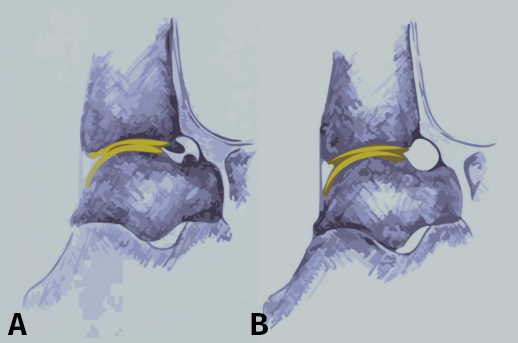

El dolor relacionado con el pinzamiento del tobillo anterior de tipo óseo está probablemente causado por la inflamación de los tejidos blandos (ligamentos, tendones), que se hallan comprimidos por los osteofitos del astrágalo y/o la tibia durante las fuerzas de dorsiflexión (Figura 1)(9,10,11). Existen varias teorías sobre la posible etiología de la formación de osteofitos que producen el síndrome doloroso de pinzamiento del tobillo anterior(12), principalmente basadas en factores mecánicos, inestabilidad crónica del tobillo, microtraumatismo recurrente y/o tracción(1,3,8,13).

Figura 1. Vista de pinzamiento óseo anterior por osteofitos. El tejido sinovial inflamado se comprime entre los osteofitos del astrágalo y la tibia durante la flexión dorsal forzada, lo que probablemente causa el dolor relacionado con el pinzamiento óseo en estos procesos.